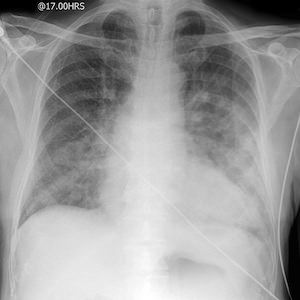

Для правильной постановки диагноза врачи используют самые различные методики. Одной их ведущих уже многие годы было и остается рентгенографическое исследование грудной клетки. При исследовании снимка здоровых легких они выглядят как светлая область, имеющая затемнения только в районе сердца и крупных кровеносных сосудов.

Если же у человека развился отек легких, просветление легочных полей крайне неравномерно. В особо тяжелых случаях наблюдается значительное помутнение, а рисунок легких визуализируется крайне плохо. Затенение на снимке легких – это именно заполнение легочных альвеол жидкостью. Хотя, справедливости ради, необходимо заметить – рентгенологическое обследование больного человека может рассказать только про наличие или отсутствие отека легких. А вот установить первопричину, которая и привела к развитию отека, при помощи рентгеновского снимка просто невозможно.